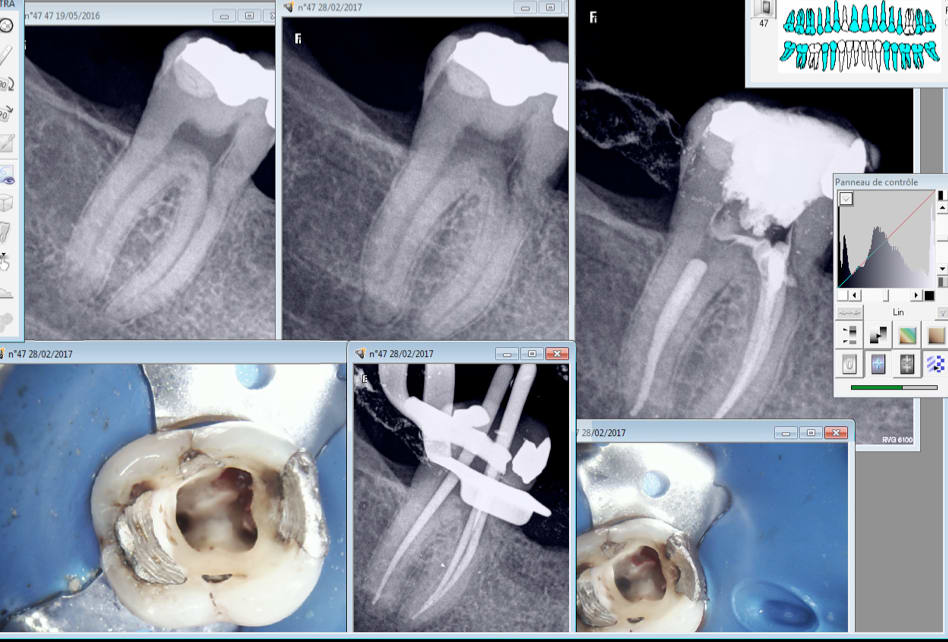

Bon alors au vu des radios d'il y a 10 mois et de la radio initiale c'est moi qui a merdé en faisant une perfo en mésio lingual ou il y avait une putain de résorbtion interne à cet endroit ?

Dent très douloureuse sans raison apparente. On a l'impression qu'il y a une zone radio claire en mésial. A l'ouverture de la chambre ca saignait à bloc !

Résorption visible sur ta cavité d'accès et à la radio , la dent est asymptomatique maintenant non ?

Je dirais plutôt résorbtion externe, mais le résultat est le même. Ce qui est con c'est qu'on le voit généralement après.....dans un premier temps on pense toujours à une superposition de la trame osseuse sur la projection radio. dejà eu quelques cas...

Celle là ca va mieux. -) Pas réussi à avoir la meme image en cone scellé et condensé en mésial que la radio cone en place.